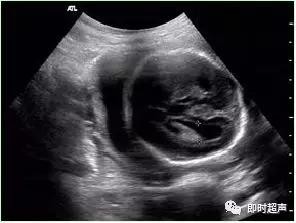

三、胎儿脑室轻度扩张(MVM)

胎儿脑室扩张是最常见的脑发育异常之一,发生率约0.03% ~ 0.15%,脑室扩张时,侧脑室后角最先受累侧脑室后角宽度作为常规衡量侧脑室宽度一个指标。

侧脑室轻度扩张 评价脑室系统体部脉络丛水平 侧脑室壁内缘测量

各种原因造成脑脊液循环受阻,积聚于脑室内,出现脑室扩张。侧脑室宽度≥15mm的明显脑室扩张称为脑积水。多为中脑导水管狭窄所致,原因包括染色体异常、炎症、肿块压迫等。